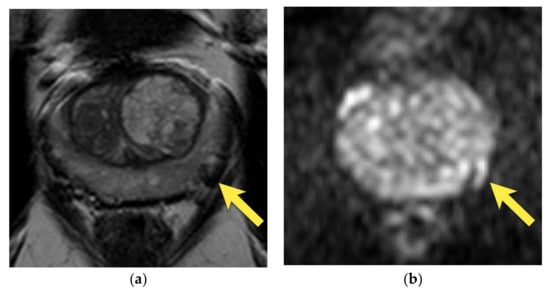

11. Quality of Images